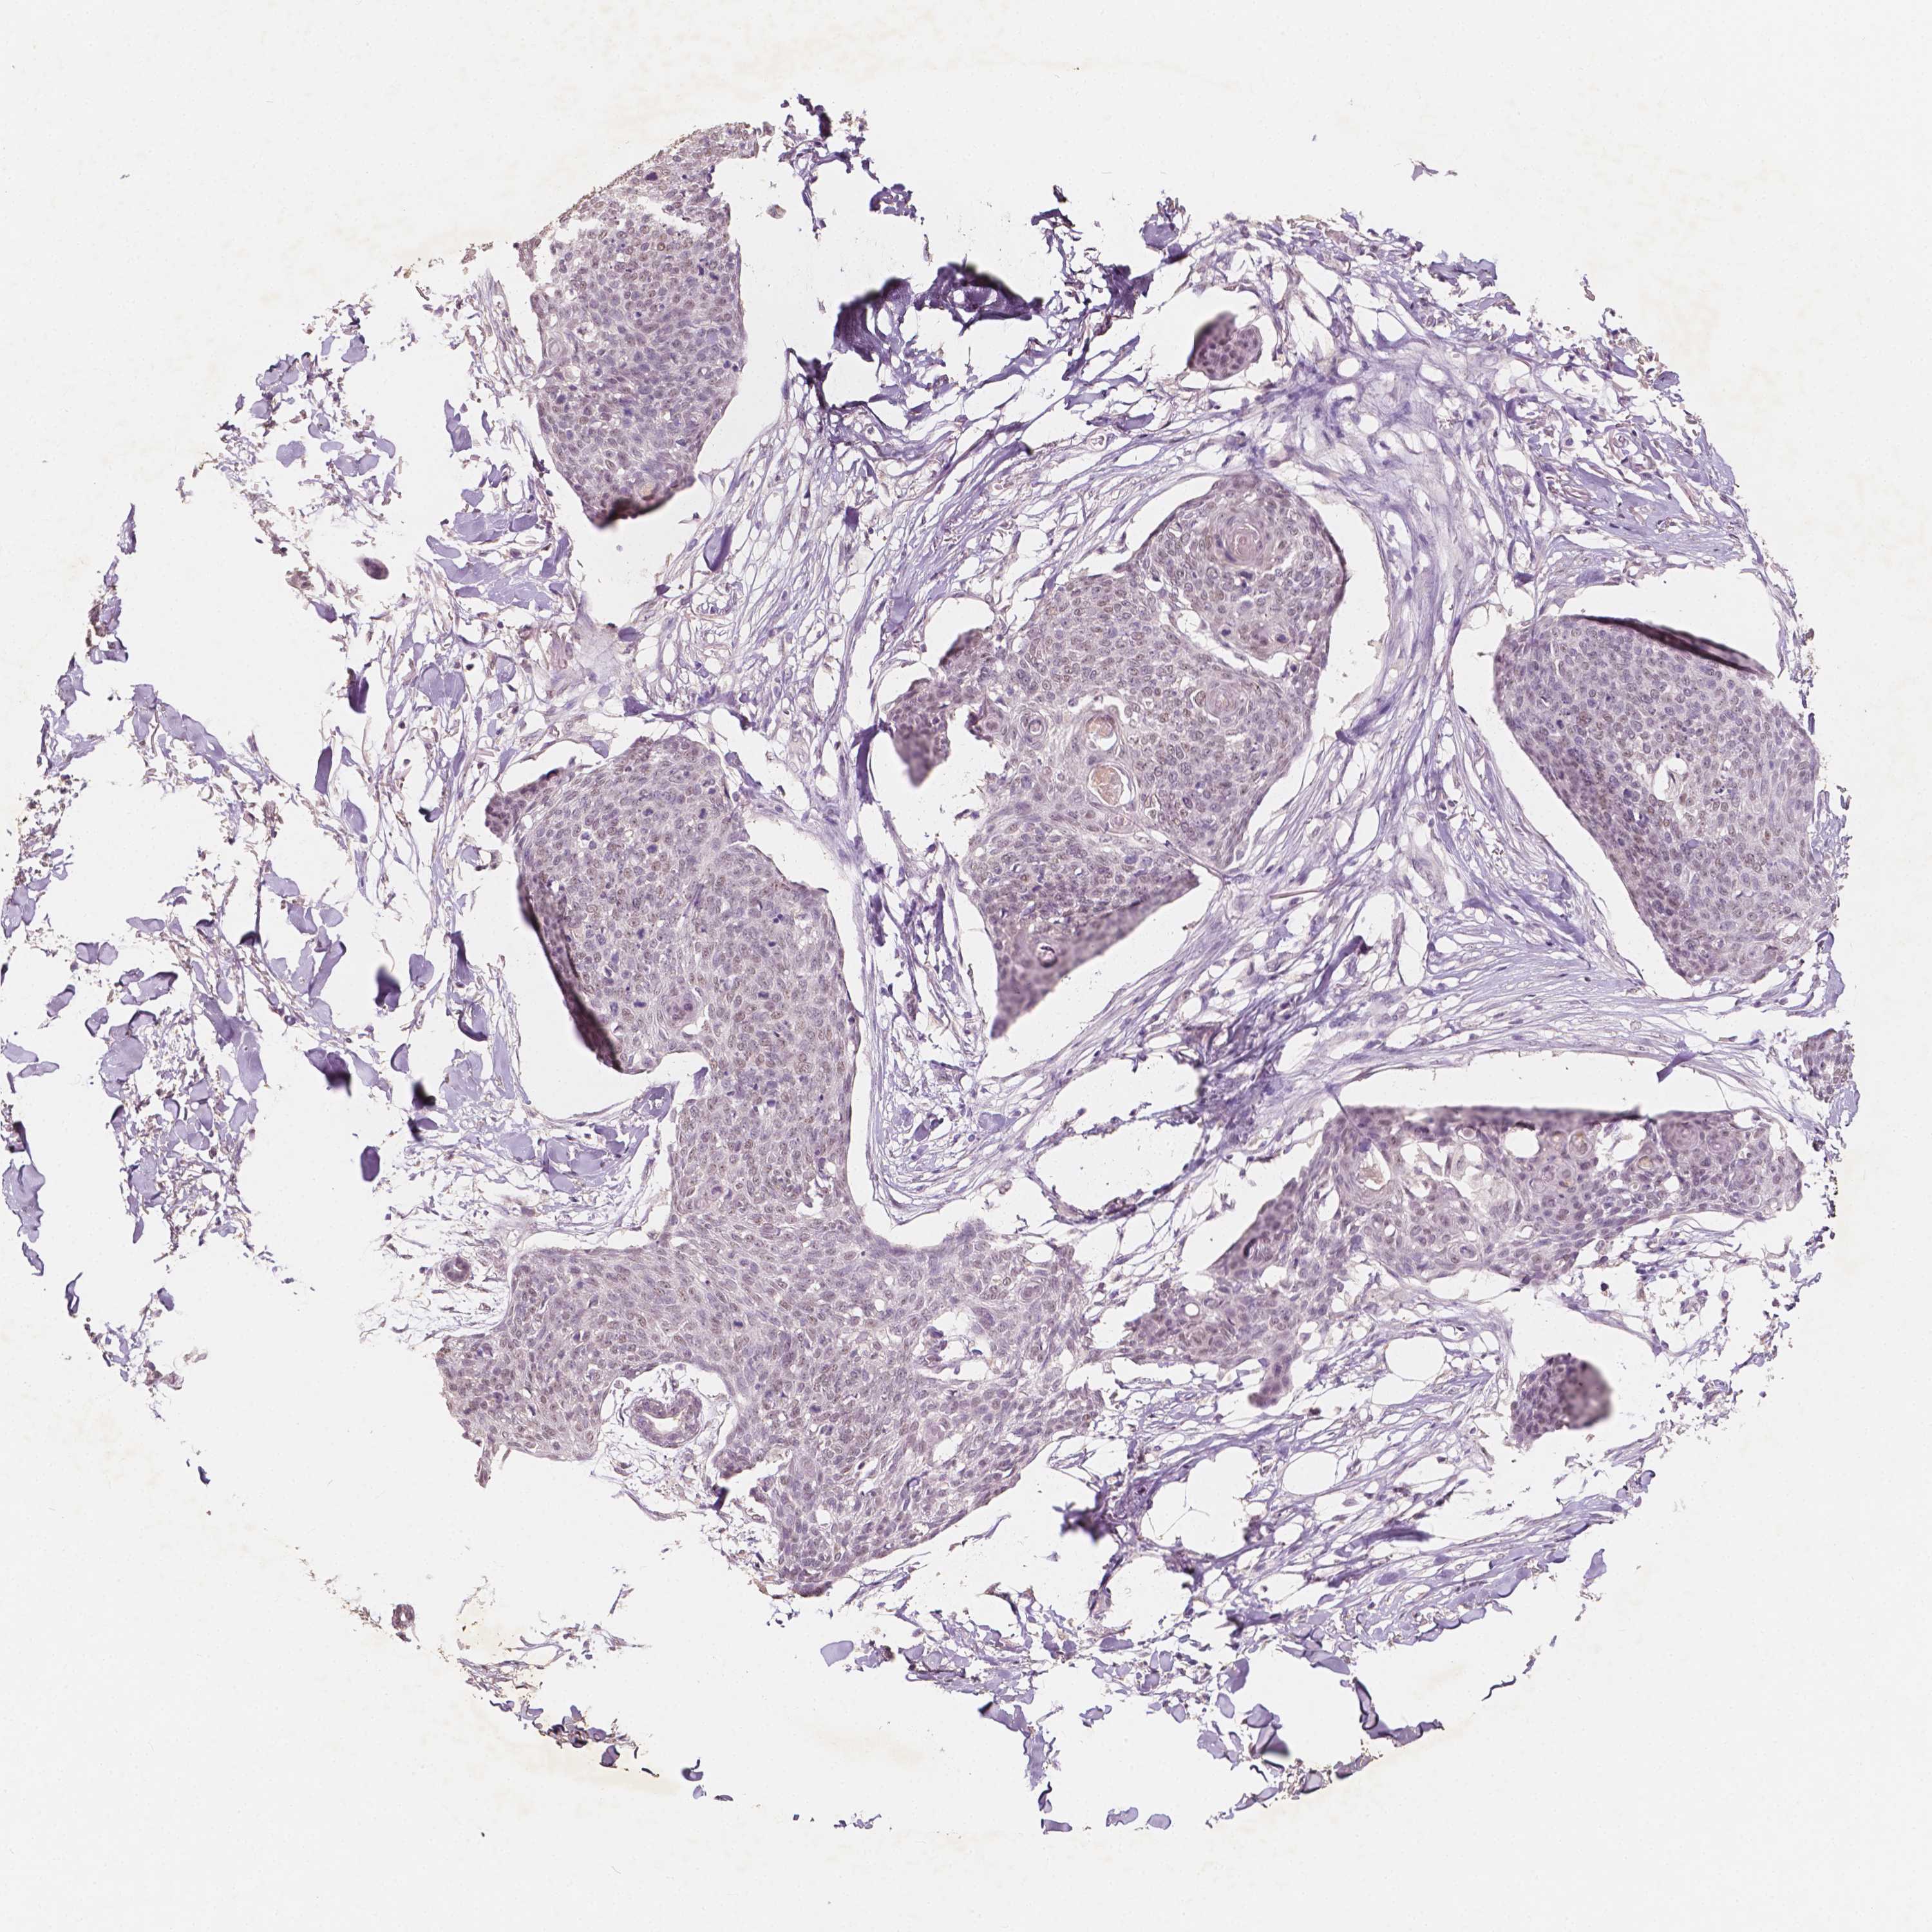

Basal cell and squamous cell cancer

SKIN CANCER - Protein expressioni

A mouse-over function shows sample information and annotation data. Click on an image to view it in a full screen mode. Samples can be filtered based on level of antibody staining by selecting one or several of the following categories: high, medium, low and not detected. The assay and annotation is described here.

Antibody stainingi

Antibody staining in the annotated cell types in the current human tissue is reported as not detected, low, medium, or high, based on conventional immunohistochemistry profiling in selected tissues. This score is based on the combination of the staining intensity and fraction of stained cells.

Each image is clickable and will lead to virtual microscopy that enables deeper exploration of all samples and also displays staining intensity scores, fraction scores and subcellular localization as well as patient and tissue information for each sample.

Antibody HPA067196

Staining

High

Medium

Low

Not detected

Intensity

Strong

Moderate

Weak

Negative

Quantity

>75%

75%-25%

<25%

None

Location

Nuclear

Cytoplasmic/membranous

Cytoplasmic/membranous,nuclear

Basal cell carcinoma

Squamous cell carcinoma, NOS